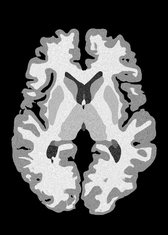

4.2 Registration to a 100 micron ex-vivo brain MRI volume

To showcase the efficacy of our method on real large scale images, we register a 250 in-vivo MRI image (Lüsebrink et al., 2017) to a 100 ex-vivo FLASH human brain volume (Edlow et al., 2019). This represents an inverse problem with more than 11.2B optimizable parameters (compared to 20M for clinical datasets), or 44.8GB of GPU memory. The entire problem does not fit on most GPUs, necessitating distributed multimodal registration. We optimize a composite transform - affine followed by a diffeomorphic mapping; details can be found in Section E.1. Multimodal deformable registration took 58 seconds on 8 NVIDIA A6000 GPUs, which is unprecedented at this resolution. Fig. 6 shows qualitative results, highlighting the ability to register highly detailed structures such as cerebellar white matter; these structures are not visible at macroscopic scales. The resultant advantages of performing registration at this scale can allow researchers to characterize the neuroanatomy at microscopic resolutions and allow morphometric analysis of cortical layers and subcortical nuclei among other structures.